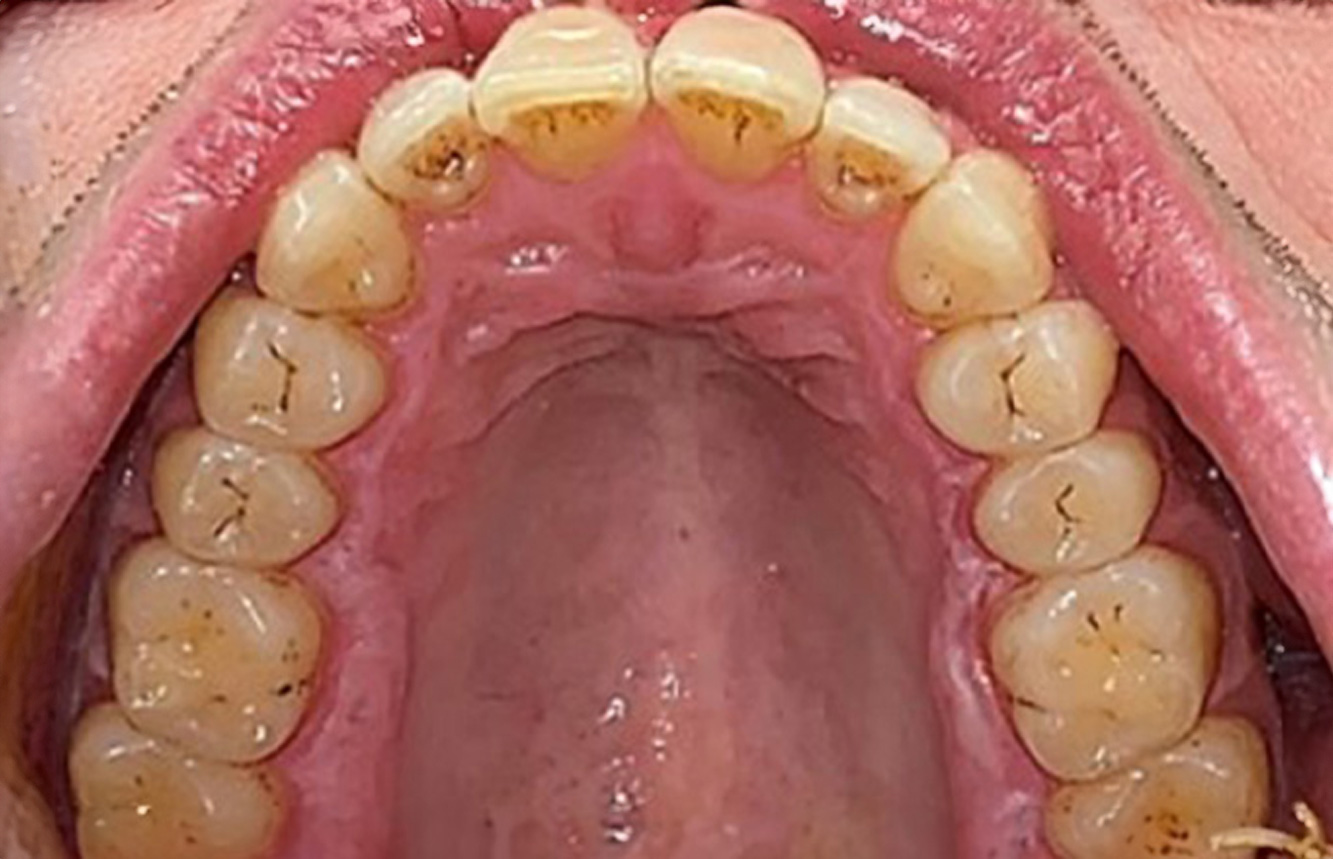

Casi di pazienti secondo l'IPCI seguenti studi di casi servono a mostrare l'interazione tra i fattori di bisogno e di rischio definiti per l'IPC così come gli effetti dei singoli fattori*. La paziente diabetica con una buona igiene oraleUna paziente diabetica di 51 anni con una buona igiene orale si presenta per una seduta di prevenzione. I valori di glicemia sono stabili con HbA1c = 6,2%, per cui si ritiene che la sua condizione possa essere sufficientemente gestita con la metformina (un farmaco per il trattamento del diabete). La paziente non presenta restauri esistenti o precedenti patologie orali. Sulla base dei referti disponibili si può constatare una gengivite nonostante una condizione altrimenti stabile. di più Case presentation: Complex Dental Prosthesis ManagementThe direct relationship between intraoral and general health, as well as the bidirectional influence that they may have on one another, is well-known (1,2). It is absolutely essential to consider both factors when planning preventive intraoral measures and treatment in the dental practice. The primary objective is the maintenance of patient health and quality of life from both dental and medical perspectives. more The (orally) healthy patient with implantsIn the medical history, the 55-year-old patient states that he has no systemic disease and is not taking any medication. The patient’s lifestyle is similarly unremarkable. The patient has a few tooth restorations and two implants (2nd and 4th quadrants). On the basis of current findings, gingivitis is identified in an otherwise stable periodontal condition on the reduced periodontium (stage III, grade A). more The healthy patient with pre-existing periodontal disease & peri-implantitisA 52-year-old patient presents at a preventive care session. The patient has no systemic disease and is not taking any medication. He has had various dental treatments and also has two active carious lesions. In addition, the patient has four implants (2nd, 3rd and 4th quadrants). He is revealed to have early periodontal disease (stage IV, grade B). His periodontal condition is stable; a probing depth of Probing depths (ST) of 5 mm is only evident at the implant in region 36. Gingivitis is also identified. more The Diabetic Patient with Pre-Existing PeriodontitisThis case report of a 52-year-old male with type 2 diabetes and periodontitis emphasizes personalized preventive measures and periodontal health maintenance to manage the moderate disease progression risk. more The 28-Year-Old Cigarette Smoker with Dental Erosions28-year-old patient, smoker, with erosions. The bidirectional relationship between oral and general medical health is very well known. It is no longer sufficient – and arguably even old-fashioned – to consider intraoral conditions in isolation. In order to create a personalized, case-specific preventive and patient profile, it is essential to take a detailed medical history and perform diligent examination of the general medical and intraoral health, as well as considering the two in combination. more Il paziente affetto da endocardite con lesioni cariose attiveIl paziente ha 39 anni e in passato è stato sottoposto ad un intervento per la sostituzione della valvola aortica dovuta a insufficienza valvolare ed endocardite. Assume regolarmente l'ASS 100 come anticoagulante. Per quel che riguarda lo stile di vita, il regime alimentare seguito dal paziente è classificato come “dieta che favorisce la formazione della carie”, per via del consumo regolare di cibi ad alto contenuto di zuccheri e dei sei-sette pasti consumati al giorno. La salute orale del paziente indica un rischio moderato di carie, con lesioni attive. Il rischio di parodontite è basso, tuttavia il paziente è affetto da gengivite. Si formulano quindi i seguenti consigli per il trattamento di profilassi. di più Il paziente trapiantato con iperplasia gengivaleSi presenta un paziente di 71 anni che ha subito un trapianto di reni e con anamnesi di ipertonia (ipertensione). Considerata la sua storia clinica, serve una terapia a lungo termine con ciclosporina che ha un effetto immunosoppressivo e amlodipina che è specifica contro l'ipertensione. Il paziente riporta anche gengive sensibili e sanguinanti. Per quanto riguarda invece lo stato di salute orale, il paziente ha un restauro, presenta un'iperplasia gengivale marcata, una parodontite allo stadio II, grado B con tasche attive e un'iniziale carie radicolare al dente 22 e in più mancano otto denti. Dalla valutazione del rischio di carie si evince un rischio moderato di carie (API 60). Per la seduta di profilassi si possono formulare i seguenti consigli per il trattamento. di più La paziente sana con precedente patologia parodontaleQuesta paziente di 68 anni non presenta alcuna patologia precedente né segue alcuna terapia che possano ritenersi rilevanti dal punto di vista odontoiatrico, e il suo stile di vita non comporta alcun rischio particolare. La paziente ha due impianti (3° quadrante, da cinque anni) e una precedente patologia parodontale (parodontite allo stadio IV, grado B) con perdita del dente. Al momento le condizioni parodontali sono stabili, tuttavia la parodontite aumenta in misura significativa le complicazioni biologiche degli impianti e c'è dunque il rischio di perdita dell'impianto (21). Per la seduta di profilassi si possono formulare quattro consigli. di più